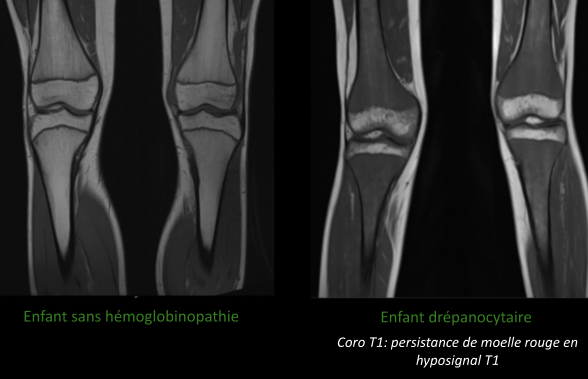

Ostéo-articulaire

- Peristance de moelle rouge dans les os longs

- Crises vaso-occlusives (Infarctus osseux, souvent multiples, l’hypersignal T1 spontané est spécifique pour le DD avec ostéomyélite)

- Ostéomyélites (DD de l’infarctus, pas évident, a suspecter si il ya des abcès, collections)